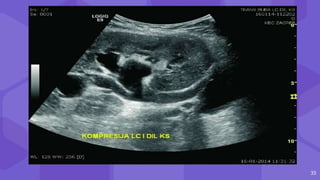

RENAL COLLECTING SYSTEM ABNORMALITIES

⬢ Obstructive hydronephrosis

⬢ flaccid or non-obstructive HN

⬢ formation of urinoma

⬢ Pyonephrosis

⬢ fungal infections

⬢ Renal stones

⬢ Transitional-cell carcinoma

(TCC).

● HN - 2-3%

● Causes : Edema

Blood clots

External compression

Stenosis d/t fibrosis

Dilatation of the collecting system of

the transplanted kidney.